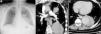

Un varón de 54 años de edad al que se había diagnosticado de enfermedad de Behçet (EB) en otro hospital, hacía 5 años, fue hospitalizado en nuestro centro por hemoptisis masiva. La radiografía de tórax mostró una opacidad bilobulada y de bordes lisos en la región hilar y paracardíaca izquierda, que no ocultaba el contorno del corazón (fig. 1a, flecha). La angiografía pulmonar por tomografía computarizada reveló 2 lesiones emergentes de las ramas superior e inferior de la arteria pulmonar izquierda, cuyas zonas centrales estaban ocupadas por material de contraste en la fase temprana del estudio de imagen (fig. 1b, flecha). La repleción de contraste se realzó durante la fase tardía del estudio de imagen (fig. 1c, asterisco). La periferia de la lesión inferior no era tan opaca y contenía pequeñas burbujas de aire (fig. 1c, flecha). Estos signos sugerían la posibilidad de rotura intrabronquial de un seudoaneurisma trombosado. Se diagnosticó una rotura de un aneurisma de arteria pulmonar (AAP), y se inició tratamiento pulsado con glucocorticoides y ciclofosfamida a altas dosis.

La radiografía de tórax mostró una opacidad localizada en la región hilar y paracardíaca izquierda (fig. 1a, flecha). La angiografía pulmonar por tomografía computarizada, reveló 2 lesiones emergentes de las ramas superior e inferior de la arteria pulmonar izquierda (fig. 1b, flecha). La repleción de contraste se realzó durante la fase tardía del estudio de imagen (fig. 1c, asterisco), observándose pequeñas burbujas de aire en la periferia de la lesión inferior (fig. 1c, flecha).